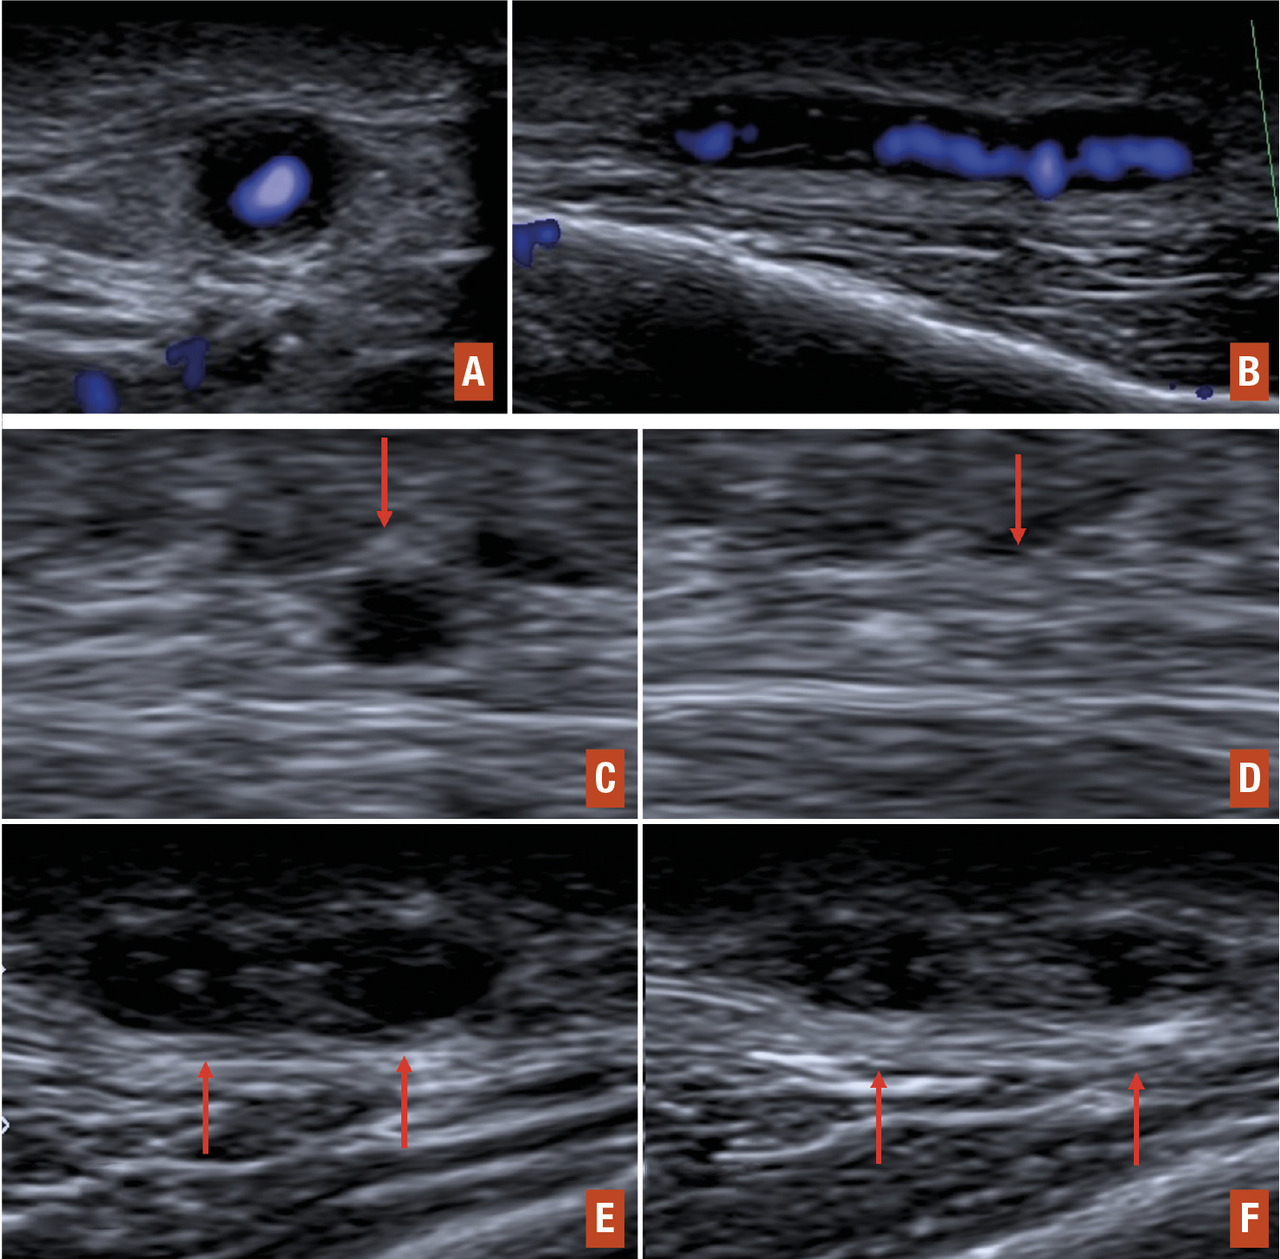

L’examen par écho-Doppler des artères temporales, s’il est effectué par un opérateur expérimenté, apparaît désormais comme un outil non invasif performant pour le diagnostic d’artérite à cellules géantes (tableau 5). Cet examen peut mettre en évidence un halo hypo-échogène (noir) circonférentiel de la paroi de l’artère temporale, une sténose voire une occlusion vasculaire complète, ou enfin un épaississement pariétal avec perte de la compressibilité de l’artère ou « signe de la compression » (fig. 4). Cet écho-Doppler est à réaliser avant la mise sous traitement ou dans les tout premiers jours du traitement, car les anomalies peuvent rapidement disparaître.

L’avantage de l’écho-Doppler est qu’il permet dans le même temps de rechercher un signe du halo au niveau d’autres artères (occipitales, faciales, axillaires, sous-clavières, carotides).